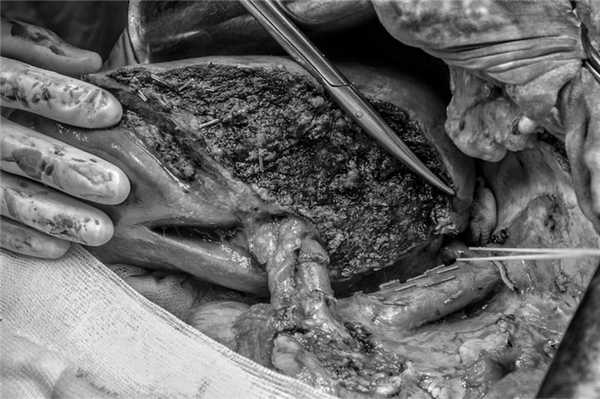

04.12.17 выполнены расширенная левосторонняя гемигепатэктомия, атипичная резекция SVI печени, холецистэктомия, атипичная резекция поджелудочной железы, иссечение паразитарной опухоли переднего средостения с резекцией париетальной плевры и перикарда. Доступ типа «мерседес». Интраоперационная ситуация соответствовала данным МСК-ангиографии: пальпаторно и визуально выявлены все очаги альвеококка. Выделены элементы гепатодуоденальной связки (рис. 6). Рис. 6. Интраоперационное фото. Выделены элементы гепатодуоденальной связки. 1 — левая печеночная артерия, 2 — правая печеночная артерия, 3 — артерия SVI печени, 4 — гепатикохоледох.

Далее мобилизованы ретропеченочный сегмент нижней полой вены, печеночные вены (рис. 7). Рис. 7. Интраоперационное фото. Мобилизованы ретропеченочный сегмент нижней полой вены, печеночные вены. 1 — нижняя полая вена, 2 — правая печеночная вена.

Левые элементы портальных ворот лигированы, Изолированный афферентный и эфферентный кровоток в остающейся правой доле сохранен. Наметилась четкая линия демаркации. Выполнены расширенная гемигепатэктомия, холецистэктомия (рис. 8). Рис. 8. Интраоперационное фото. Правая доля печени с сохраненным афферентным и эфферентным кровотоком.